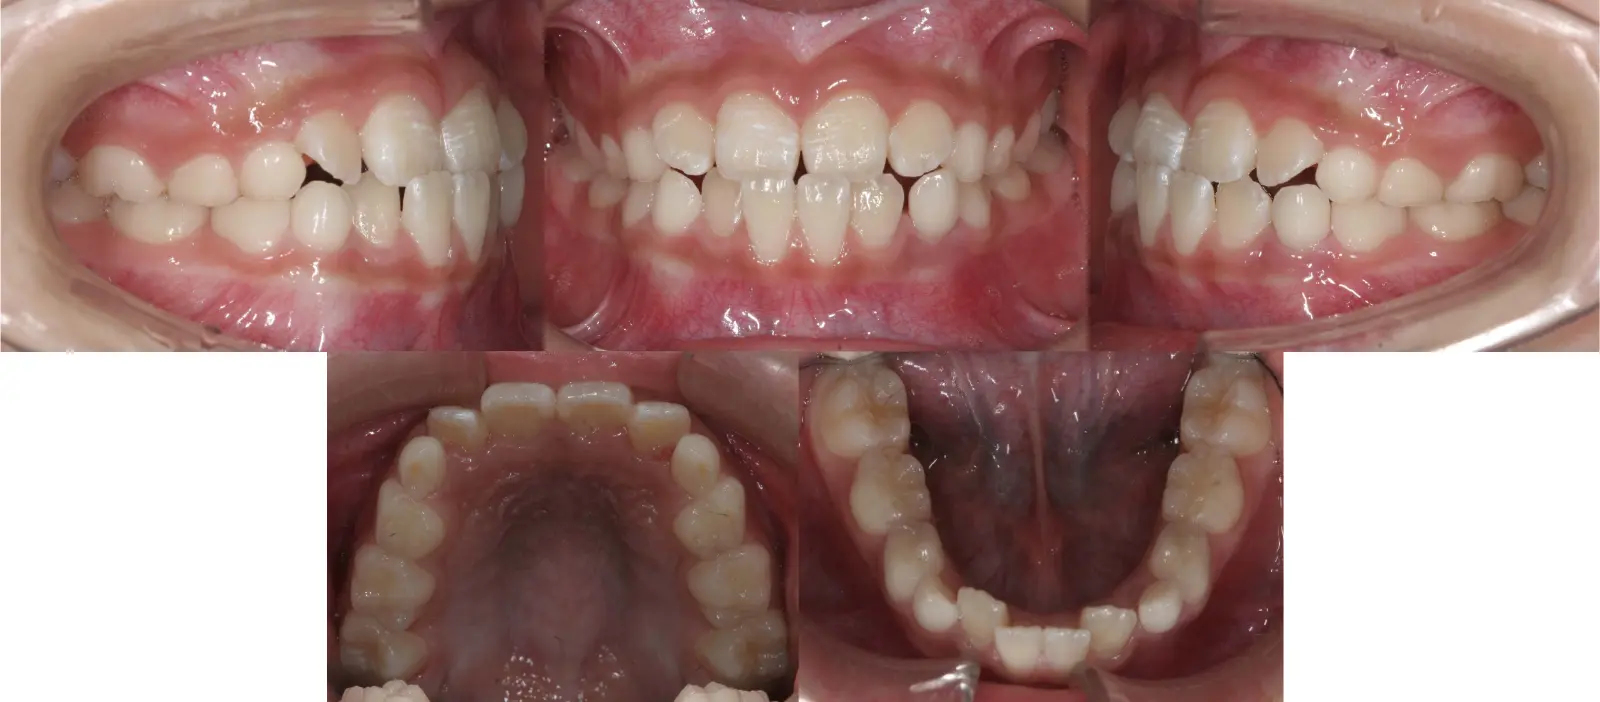

アングルⅡ級 軽度叢生を伴う下顎前突症

第一段階の治療のみで、

永久歯は問題なく萌出し、安定している

- 主訴

歯のガタガタと切端咬合

- 年齢

8歳

- 治療期間

1年3ヶ月

- 治療回数

7回

- 治療に用いた主な装置

2by4、フェイシャルマスク、拡大床

- 治療費

400,000円(税別)トータル料金

- 抜歯部位

非抜歯